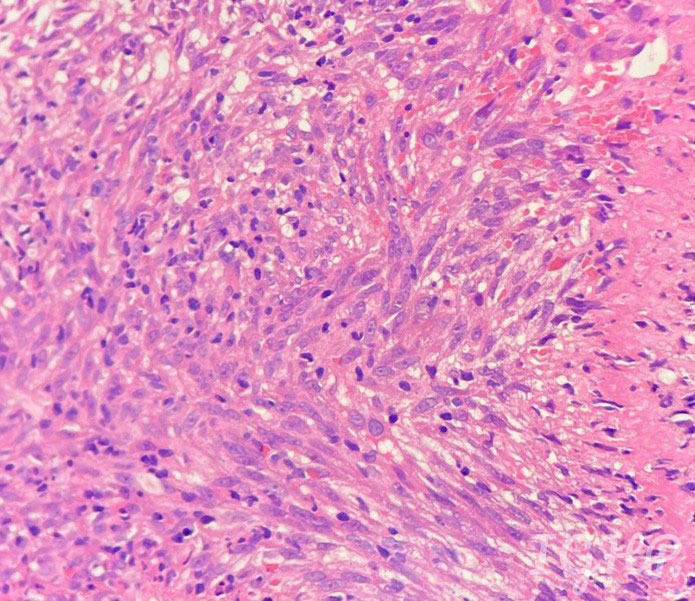

Microscopic Images-

Histology images showed bits of ulcerated small bowel mucosa with presence of proliferated spindle cells in ulcer bed.

Immunohistochemistry performed showed the atypical spindle cells are positive for CD34, CD117 and DOG1. Ki67 index is 5-6%.

Gastrointestinal Stromal Tumours are usually found in stomach (50% to 60%), followed by the small intestine (30% to 40%). GI Bleeding is most common presenting complaint. The spindle cells are positive for CD117(C-KIT protein), a tyrosine kinase growth factor receptor along with DOG1 and CD34.